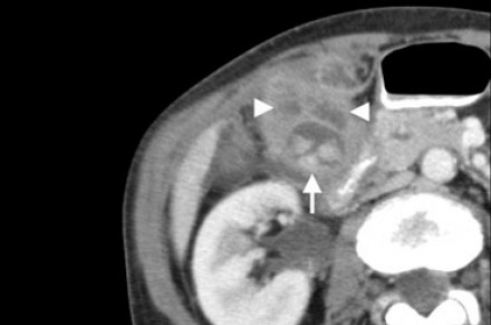

(Слева) На аксиальной КТ с контрастным усилением определяется частичное обызвествление стенки желчного пузыря. Обратите внимание на плохо различимое образование мягкотканной плотности в просвете желчного пузыря и нечеткую границу с прилежащими отделами печени.

(Справа) На аксиальной КТ с контрастным усилением визуализируется дискретное объемное образование в желчном пузыре («классическая» картина рака желчного пузыря). Для рака желчного пузыря более типичным является ограниченное, а не диффузное обызвествление стенки.

Острый калькулезный холецистит. После контрастного усиления визуализируется растянутый желчный пузырь (белые наконечники) со слегка утолщенной стенкой. Визуализируется камень в шейки желчного пузыря (белая стрелка).

Выше представлено КТ пациента 71 года с ксантогранулематозным холециститом. Постконтрастное КТ. Визуализируется утолщение стенки желчного пузыря с включениями, которые соответствуют абсцессу или фокусам воспаления.